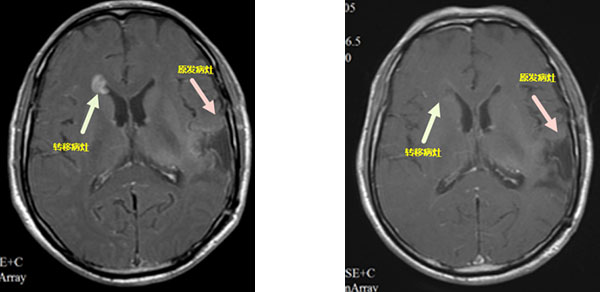

(2)

放疗前 放疗后